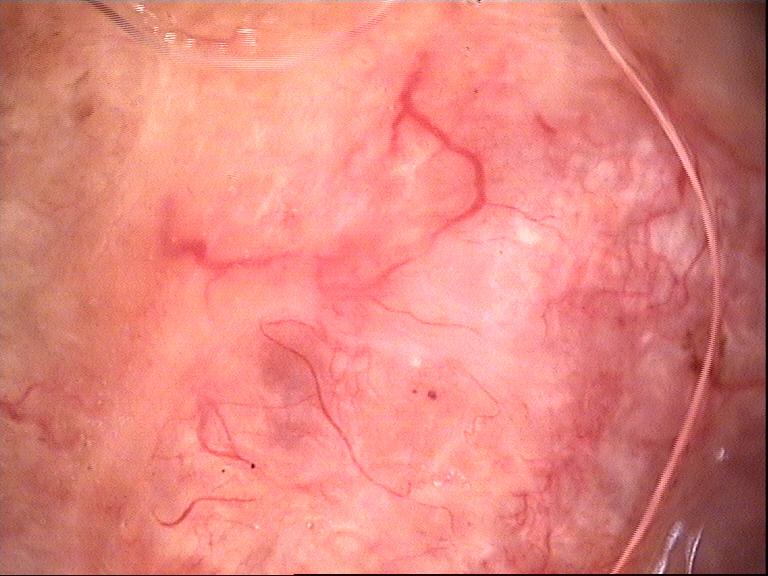

ISIC_4040190

Clinical

Field

Value

diagnosis_1

Benign

diagnosis_2

Benign melanocytic proliferations

diagnosis_3

Nevus

diagnosis_4

Nevus, NOS, Junctional

image_type

dermoscopic

melanocytic

True

patient_id

IP_3293072